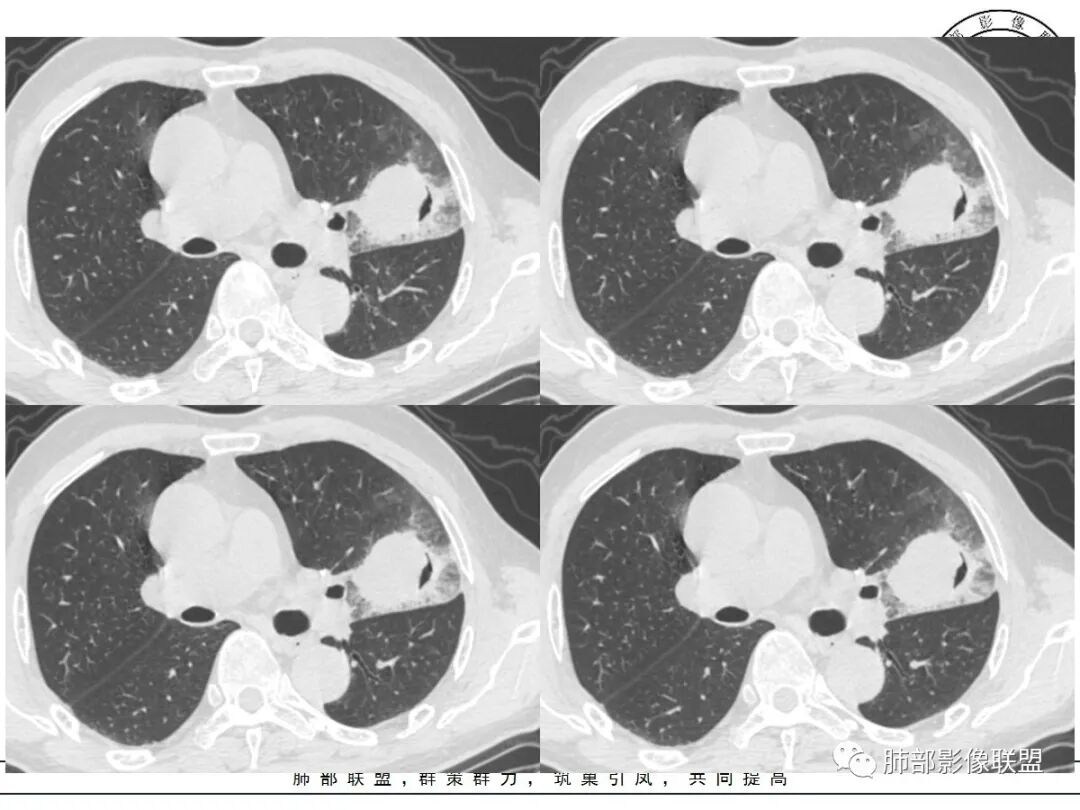

这三个月后的

发了后面这个,就不用纠结了,直接秒了。

大雄:

我只是要告诉大家,不是二元,就是肿瘤,没有什么感染,磨玻璃都没消失。

周围磨玻璃影是飘出去的粘液,也是肿瘤的一部分吧?

尘缘:

@小赵 这个不一定是粘液,很可能还是周围癌性浸润。看术前复查,原磨玻璃区呈明显小叶间隔增厚改变了。说明还是癌性淋巴浸润。

@温附一影像科,傅钢泽 应该是STA(气腔播散)加癌性淋巴管炎。

支气管稍扩张→有张力,GG0边缘清楚,局部有小叶间隔阻挡。

反思,恶性膨隆,远端空洞,强化坏死不均,里面血管似乎也是增粗,边界不清,似乎有侵犯。坏死还是边界不清。

5、周围磨玻璃,3个月后逐渐转为密实,应符合当初附壁生长为主,且逐渐向实体成分转换。

6、病变长轴平行且受限于胸膜,外围大内带小,符合外朝内发展病变。“腔内结节状明显强化”加之支气管改变有力支持新生物诊断。如此大范围边界不清的磨玻璃影让人浮想联翩。如此大范围病灶,肺门纵隔未见肿大淋巴结也让人意外。